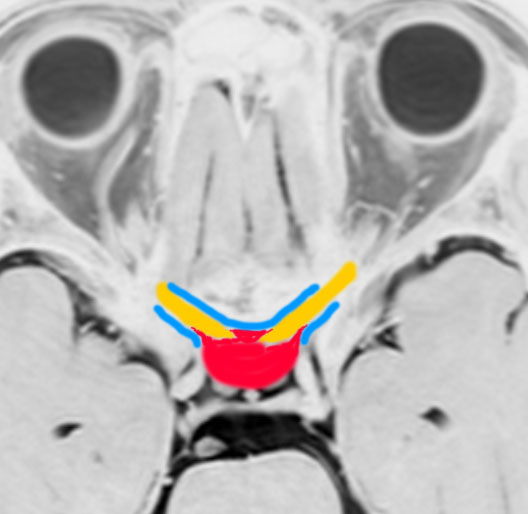

この図のように,視神経(黄色)は,骨(青色)で形成される視神経管の中を走行して頭蓋内へ入ります。視神経管は骨ですから,この狭い管の中に腫瘍が入ると視神経が腫瘍の圧迫でつぶれてしまって,視力障害を出しやすいです。

鞍結節髄膜腫(赤色)はこの視神経管の中に浸潤して伸びていく性質を有しています。ですから,視神経管の骨を削って,視神経管の中に潜り込んでいる腫瘍を根こそぎ摘出しないと,再発する可能性が高いです。